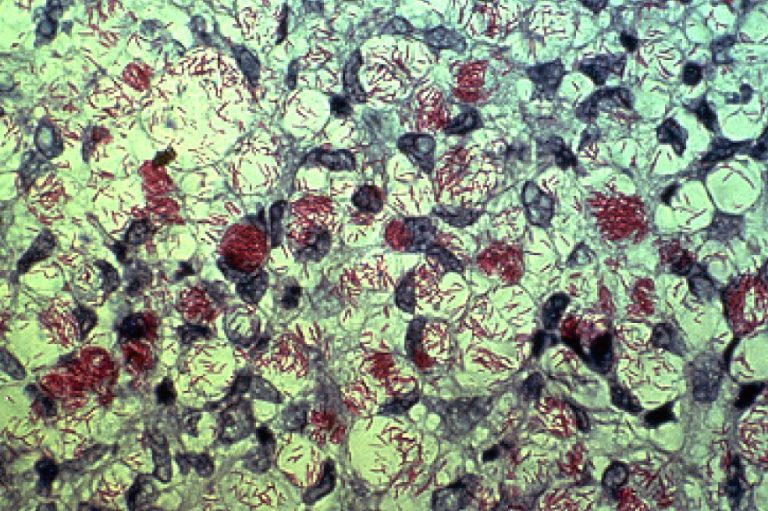

En 2017 hubo más de 210 mil nuevos casos y aparecieron varias cepas que demostraron resistencia a...